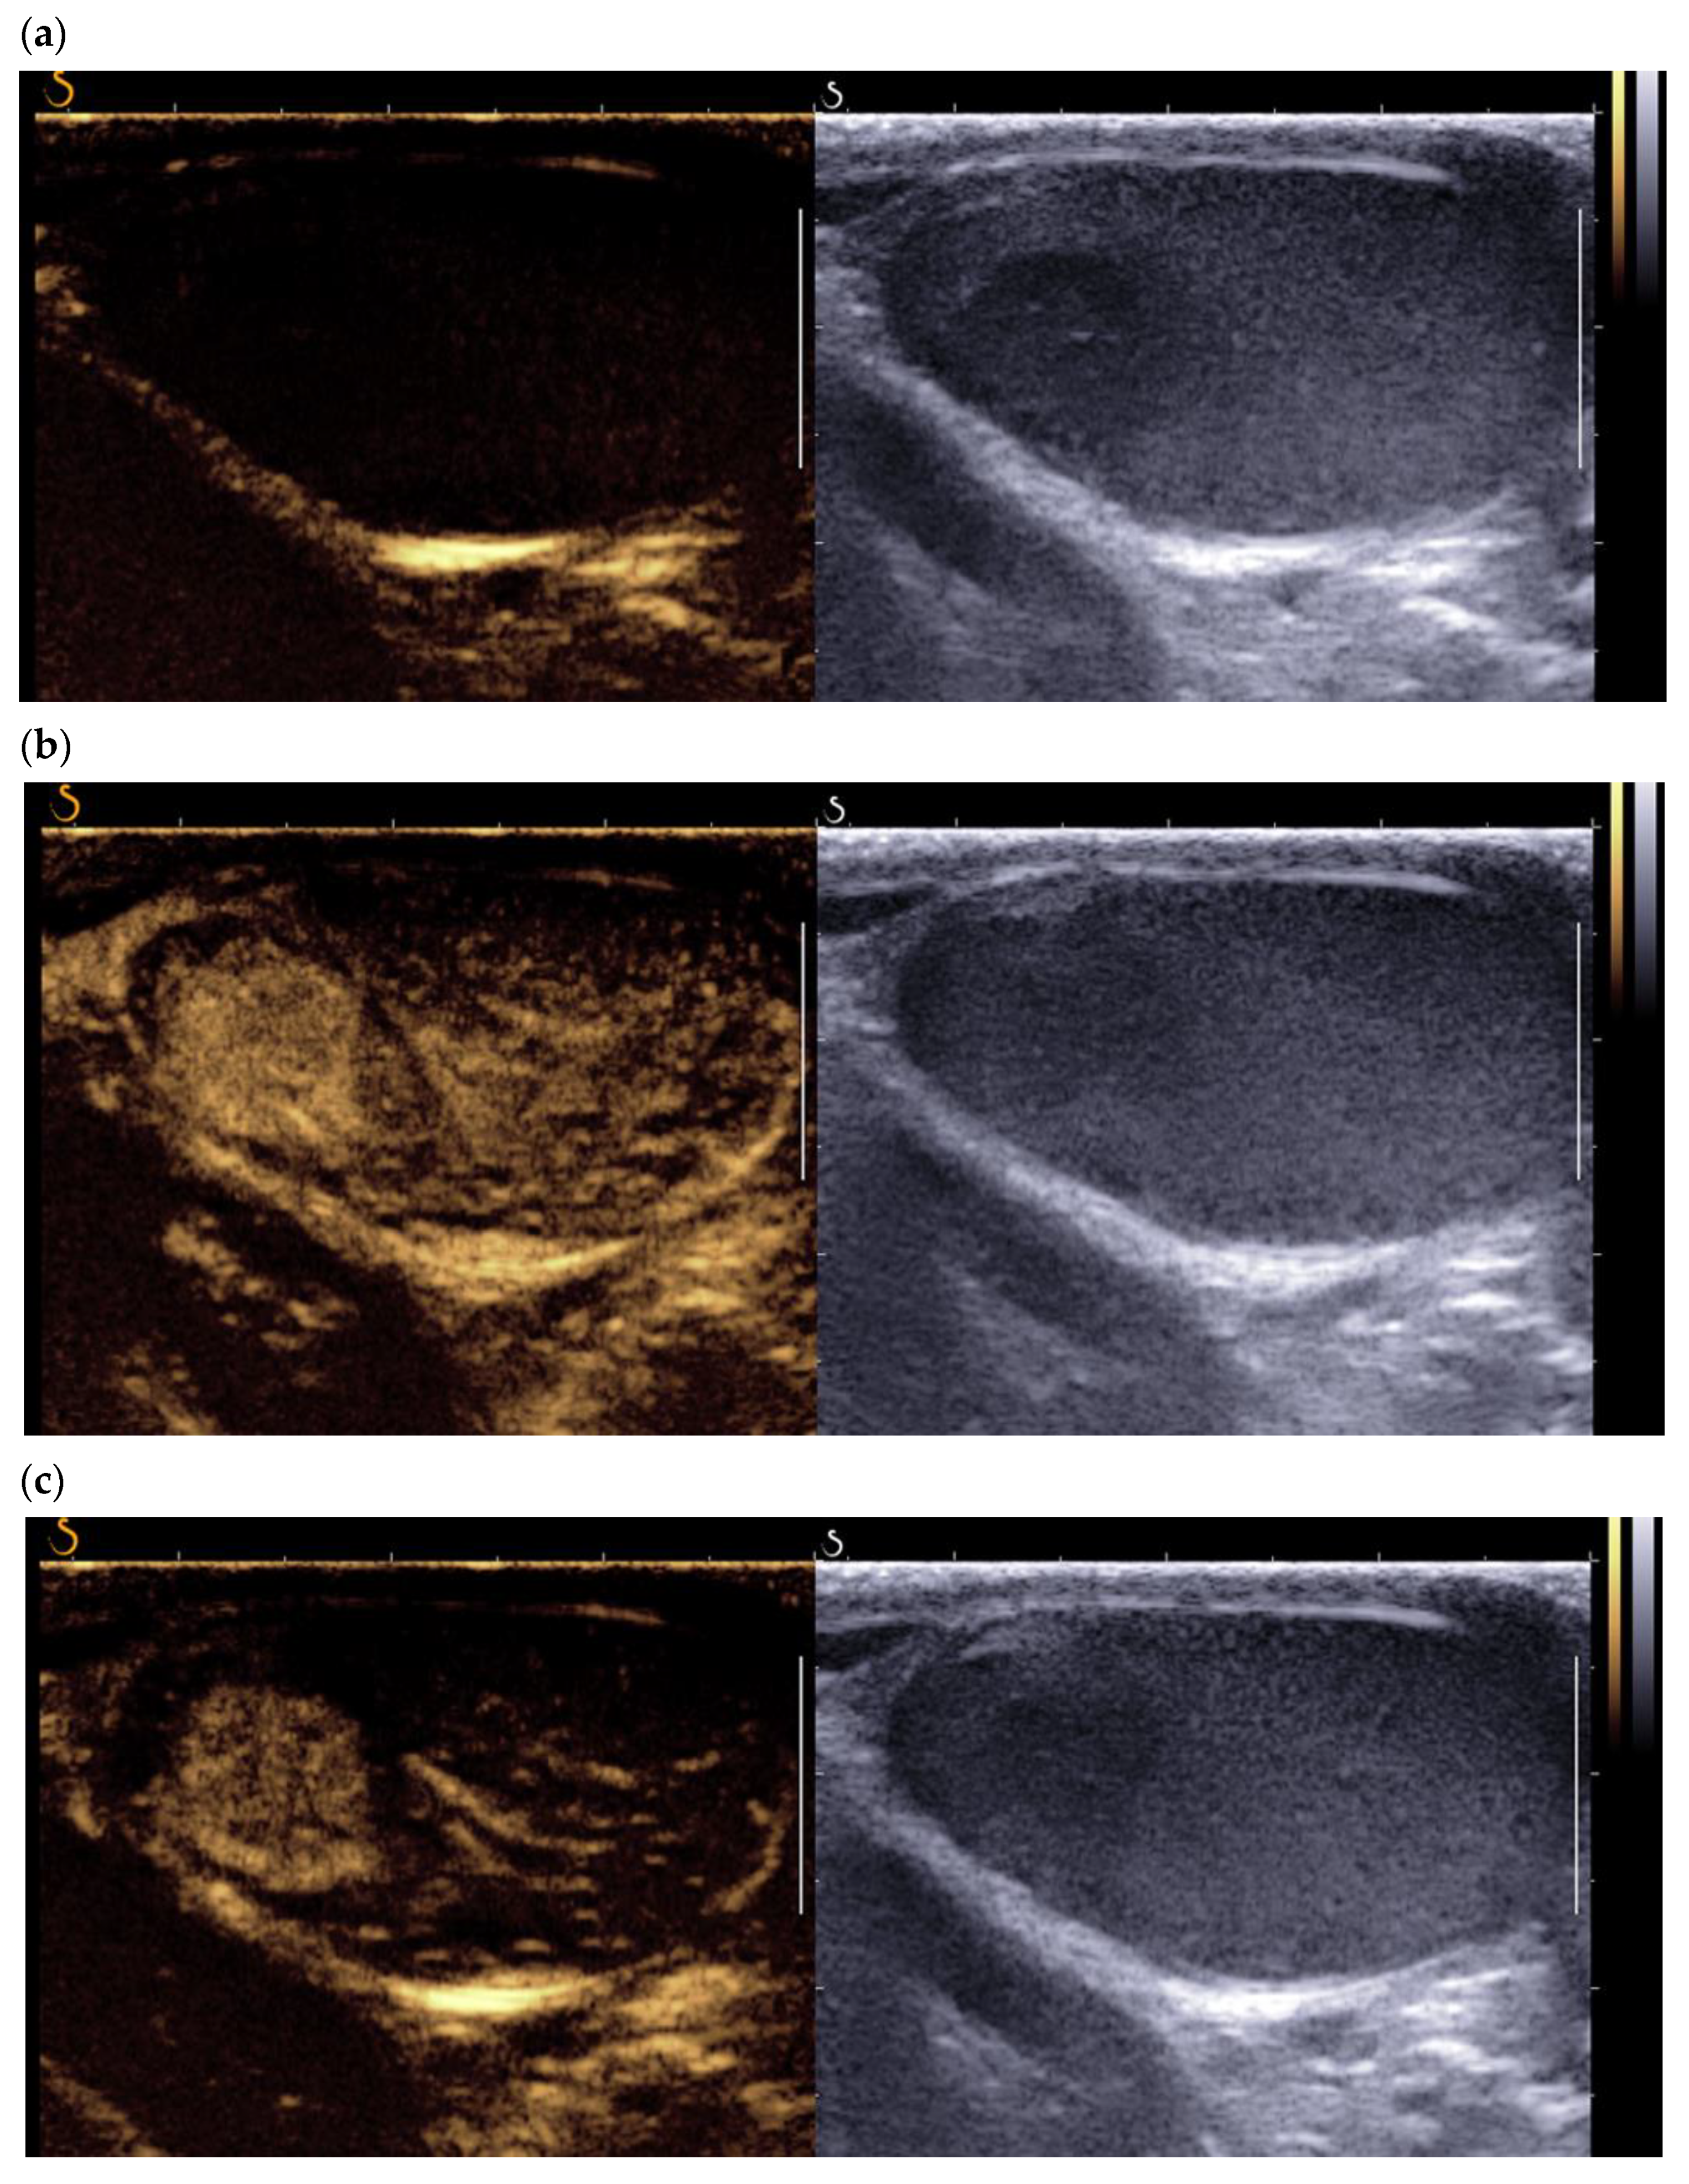

3.3. Contrast-Enhanced Ultrasound

The PubMed search using contrast-enhanced ultrasound-CEUS/contrast-enhanced ultrasound yielded 15 references, including four case reports. Through the intravenous injection of microbubbles (Sonovue® or Sonozoid ®), (CEUS) allows for qualitative and quantitative analysis of testicular and lesion enhancement. The first studies using CEUS showed that LCTs present early enhancement and that a feeding vessel in the periphery of the tumor could be identified [13,17]. This pattern can also be found using color Doppler (Figure 2b). Lock et al. reported that the CEUS quantitative parameters of time-intensity curves did not distinguish LCTs from seminomas [13]. This was confirmed by Luzurier et al. in their study of 15 LCTs all of which presented early enhancement, followed by wash-in compared with the adjacent pulp (Figure 4) [15].

Figure 4.

Contrast-enhanced ultrasound using Sonovue® of a typical LCT (a) t = 0 s (b) t = 30 s (c) t = 60 s found in a 45-year-old patient addressed for infertility work up.

No significant difference was found between the contrast enhancement of LCTs and that of active malignant testicular tumors. More recently, Drudi et al. found no significant difference between the enhancement pattern of LCTs and of seminomas, even though the quantitative parameters of the time-intensity curves differed significantly (shorter time to peak and higher peak enhancement) [17,18,19]. The authors explained this difference by the greater density and regularity of the vessels of LCTs. Vandaele et al. reported that LCTs presented very rapid and perfectly homogeneous enhancement, whereas the enhancement of seminomas was rapid but with heterogeneous kinetics [20]. These data are, however, subjective and difficult to treat for lesions < 5 mm. As previously stated, color Doppler cannot always correctly assess the vascularization pattern of very small lesions. However, using CEUS, Auer et al. reported improved sensitivity in the detection of vascularization of tumors < 5 mm, without discrimination between seminomas and LCT [21]. Overall, CEUS differentiates active solid tumors from burned-out tumors but does not yet effectively discriminate LCTs from seminomas, the main differential diagnosis. The use of quantitative data extracted from enhancement curves, which requires post-treatment work, is difficult to apply in routine practice. This modality is nonetheless part of a body of evidence based on ultrasound and multimodal MRI data.